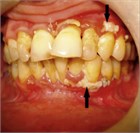

患者は歯肉全体の激しい痛みを訴え,しばしば味覚異常や,酷い口臭を伴うようになる.歯肉は腫状となって発赤を伴い,歯間の歯肉には灰白色の膜様の壊死組織が生じる.歯肉は易出血性となり,歯肉組織,特に歯間乳頭が失われる.最終的には歯の動揺が起こり,発熱や脱力感を伴う全身性の感染徴候が現れることがある.